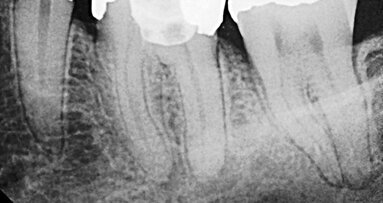

The following is a case study of a 50-year-old female with a history of a failing root-filled, upper-left central incisor. The root filling had been present for approximately 25 years and this had been apicected approximately 13 months before the tooth became problematic (Fig. 1).

Once the tooth was removed, the socket walls were curetted to remove any remnants of periodontal fibres or granulation tissue. The socket was inspected to ensure that the buccal plate was still intact (Fig. 3).